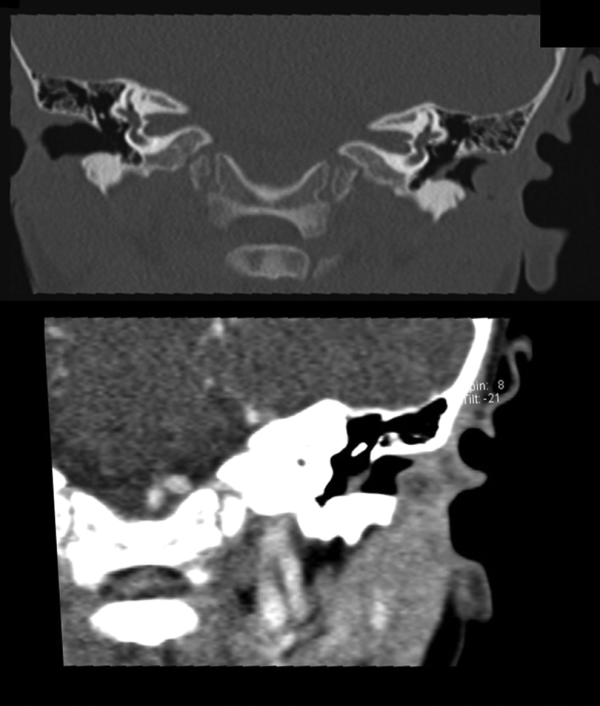

Figure 2

Preoperative computed tomography frontal scans before (upper image) and after (lower image) contrast medium application, revealing an oval tumor limited to the cartilaginous part of the left external auditory canal. These images show no imminent erosion of cartilage or spread to the surrounding tissue and mild peripheral contrast enhancement.